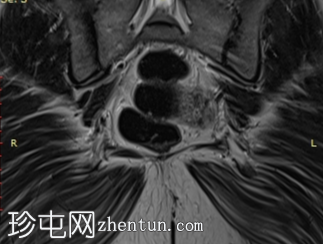

矢状位

T2加权像

宫颈可见多个呈分叶状排列的小囊性病变。

MRI通常显示双侧对称性卵巢增大、均匀T2低信号和轻度间质强化。可见外周卵泡,但数量少于多囊卵巢综合征(PCOS)患者。这些发现与卵巢间质肥大和黄素化卵泡膜细胞相符,这些特征符合卵巢卵泡膜增生症的诊断。